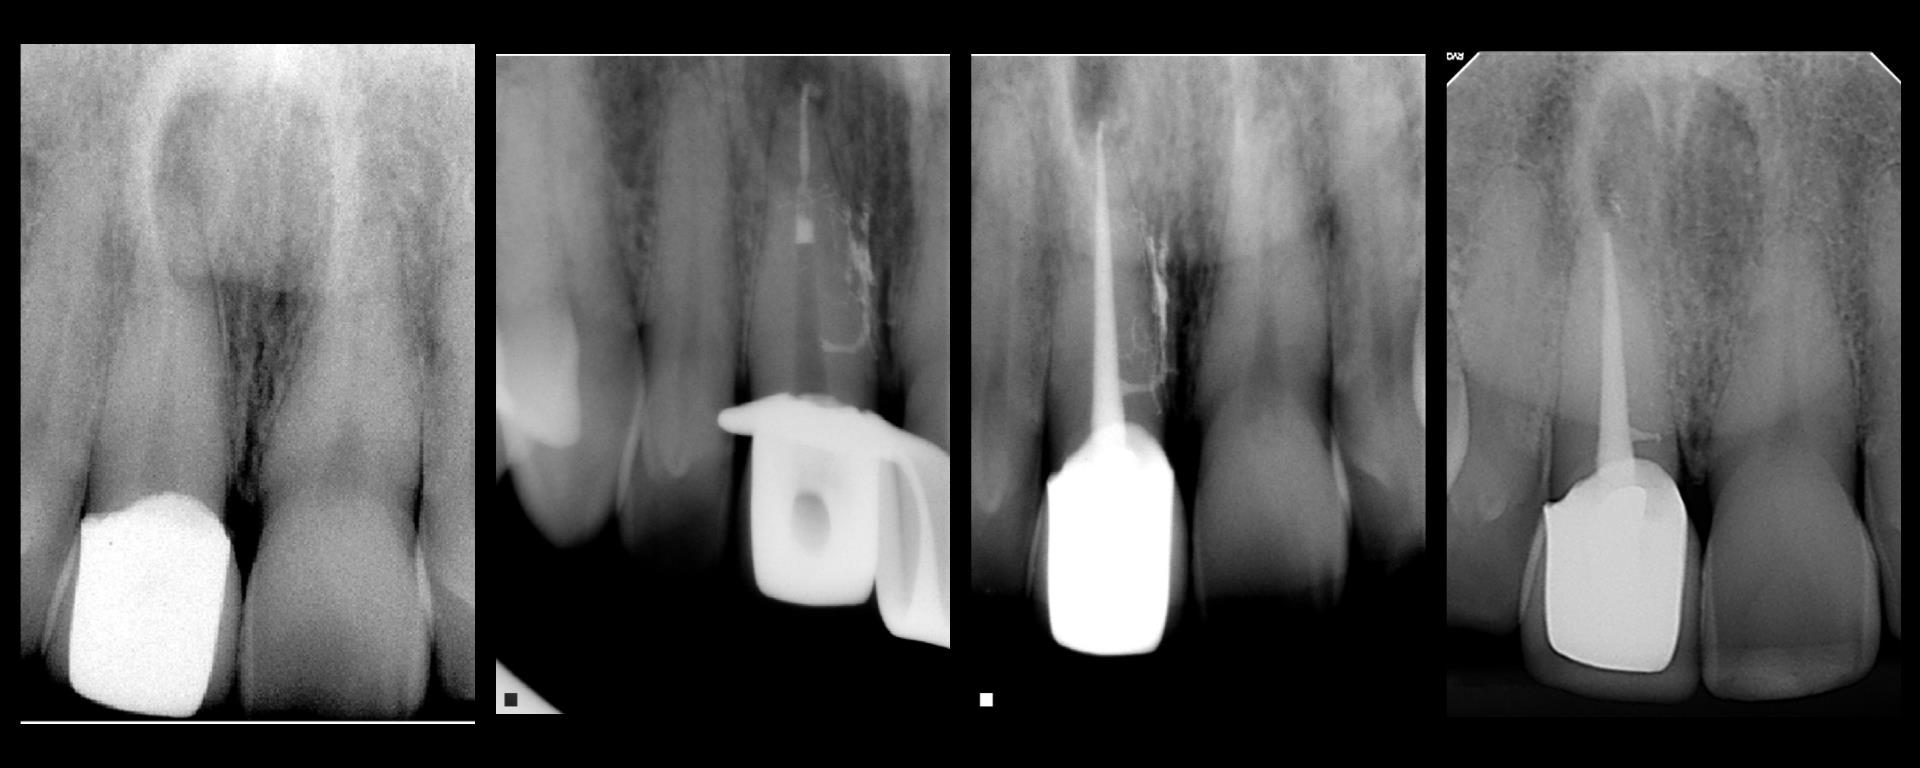

20 yr recall today

July 20, 2018 1 comment

Don you just love anterior teeth recalls?